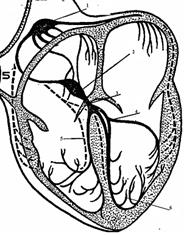

ФІЗІОЛОГІЯ СЕРЦЯ

Фази серцевого циклу

Фази серцевого циклу

ФІЗІОЛОГІЯ СЕРЦЯ